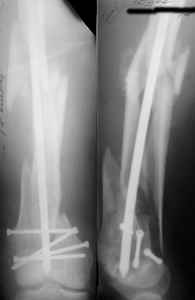

I presented a series of ~25 such cases at EuroTrauma'2004. Many cases were discussed here. I attach am example. Look also recent cases at http://www.hwbf.org/hwb/conf/alex58/scfx.htm,

THX, initial images are

1,

2.

At that moment we had in stock only the 10 mm solid nails so of course there was no idea about early weight bearing. But it was quite enough for early knee ROM excersises (see attached). Two locking screws through the distal block provided that.